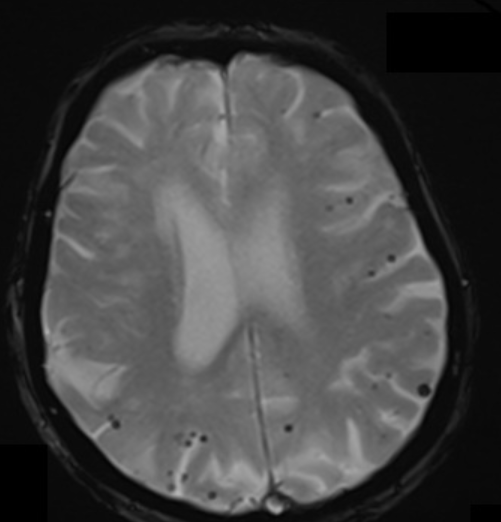

Patient with dementia has this imaging finding. What is the most common presentation of this disorder?

Cerebral amyloid angiopathy, most common presentation = spontaneous lobar hemorrhage